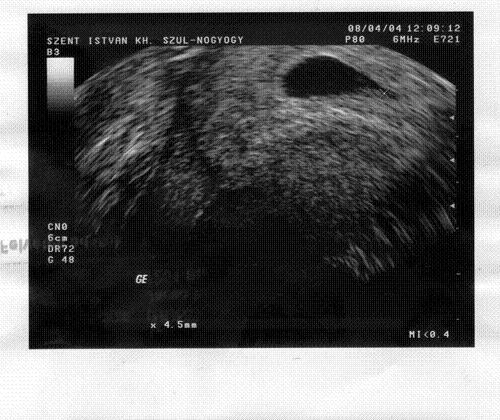

Gyurmi! Ne izgulj! Látszik, hogy van ott babóca. Ezek a tanácsok (fiút vagy lányt) valakinek bejöttek?